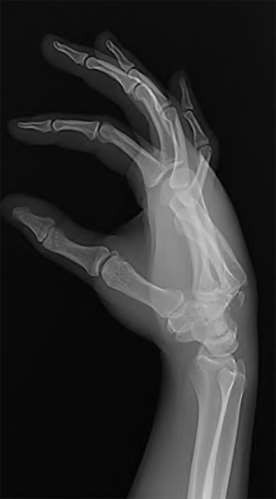

A 35-year-old woman reports wrist pain after a fall onto an outstretched hand. On exam, she has focal tenderness over the wrist snuffbox. A radiograph and CT image are shown in Figures A and B. What is the proper treatment of her injury?